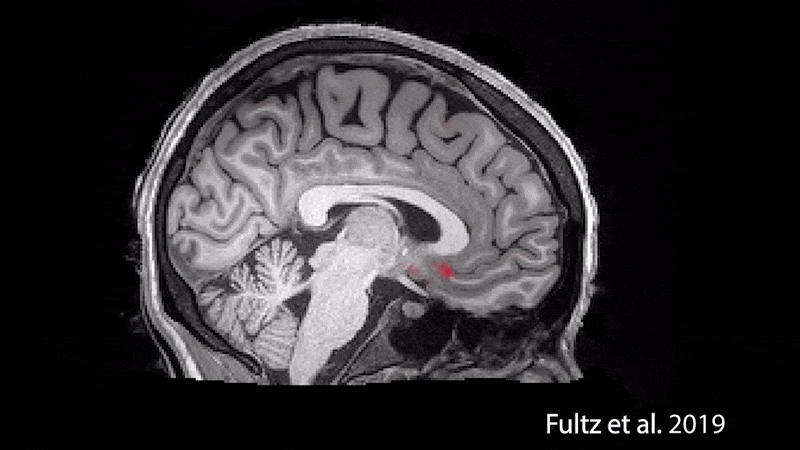

2019년 연구자들은 functional MRI로 피험자들의 수면 시 뇌척수액의 흐름(pulsing wave)을 촬영하여 눈으로 확인하였습니다.

수면 시 뇌혈류(붉은 신호)와 뇌척수액의 흐름(파랑 신호) (Image: © Laura Lewis])